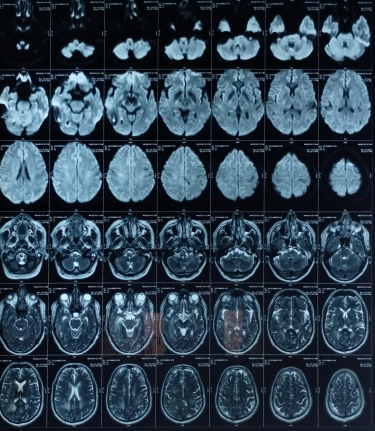

The patient’s routine blood investigations were normal. Serology for HIV, hepatitis B, C, and syphilis was negative. His MRI brain showed a parenchymal bleed in right temporo occipital regions with intra-ventricular leakage of blood and tiny petechial haemorrhage in brain parenchyma bilateral. extensive signal changes in cerebellar hemisphere, bilateral gangliothalamocapsular region, pons, midbrain and deep white matter of both cerebral hemisphere? Microangiopathy? CADASIL.

Early-onset dementia (onset before age 65) is a thought-provoking ailment with many possible causes, including early-onset familial Alzheimer’s disease, frontotemporal lobar degeneration, Parkinson’s dementia, Lewy body dementia, disorders of amino acid and organic acid metabolism, leukodystrophies, lysosomal storage diseases, disorders of metal metabolism, and mitochondrial diseases [6]. In our patient, the history, physical examination, laboratory investigations, and neuroimaging were not suggestive of these causes and prompted the search for a rare etiology. The most common MRI finding associated with CADASIL is basal ganglia and white matter hyperintensities in T2-weighted sequences that start as punctate or nodular foci and then often become confluent, extensive, and usually symmetrical, mainly in the periventricular region, anterior temporal pole, external capsule, the centrum semiovale, and frontal and parietal areas. In our patient, diagnosis was made mainly from MRI findings as seen in fig. 1, 2.

Fig. 2: Extensive hyperintensity on T2W/FLAIR sequence is seen in bilateral thalamus and basal ganglia, both cerebellar hemisphere, mid brain, pons and in deep white matter of both cerebral hemispheres